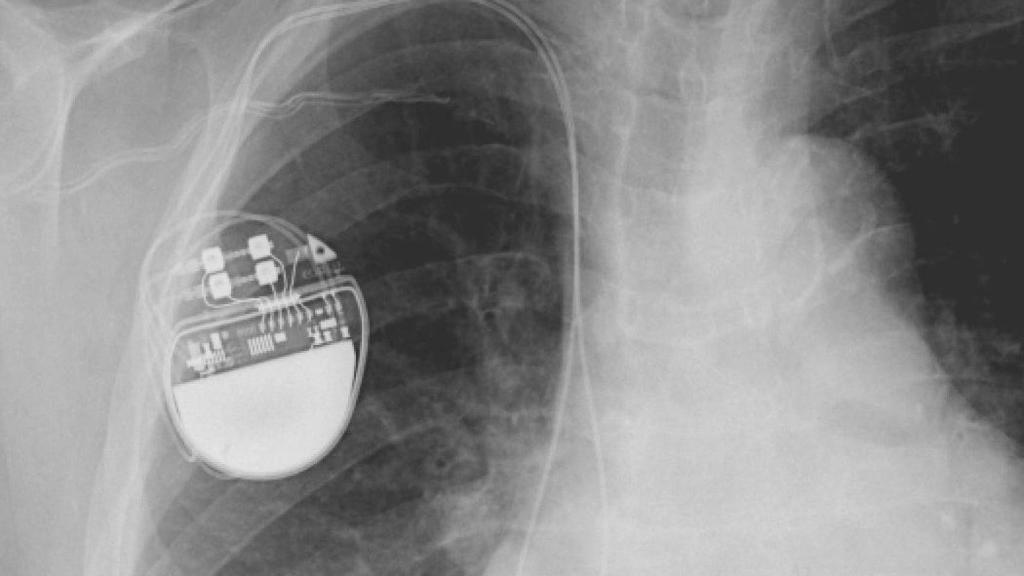

Un marcapasos tradicional.

Un marcapasos dentro de un cuerpo humano.